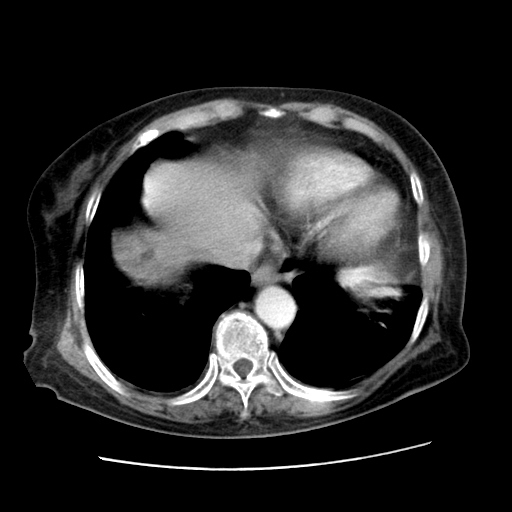

女,77.无不适

肝内胆管扩张,胆囊炎,胆囊窝积液。 右侧胸腔少量积液。

肝脏变异

右侧胸腔少量积液(也可能是胸膜增厚不过是什么都一样)

胆囊未见明显显影

肝脏变异、异位胆囊,肝右叶肝内胆管结石并肝内胆管扩张。

肝右叶肝内胆管结石并肝内胆管扩张。另:慢性胆囊炎!胆囊窝积液!